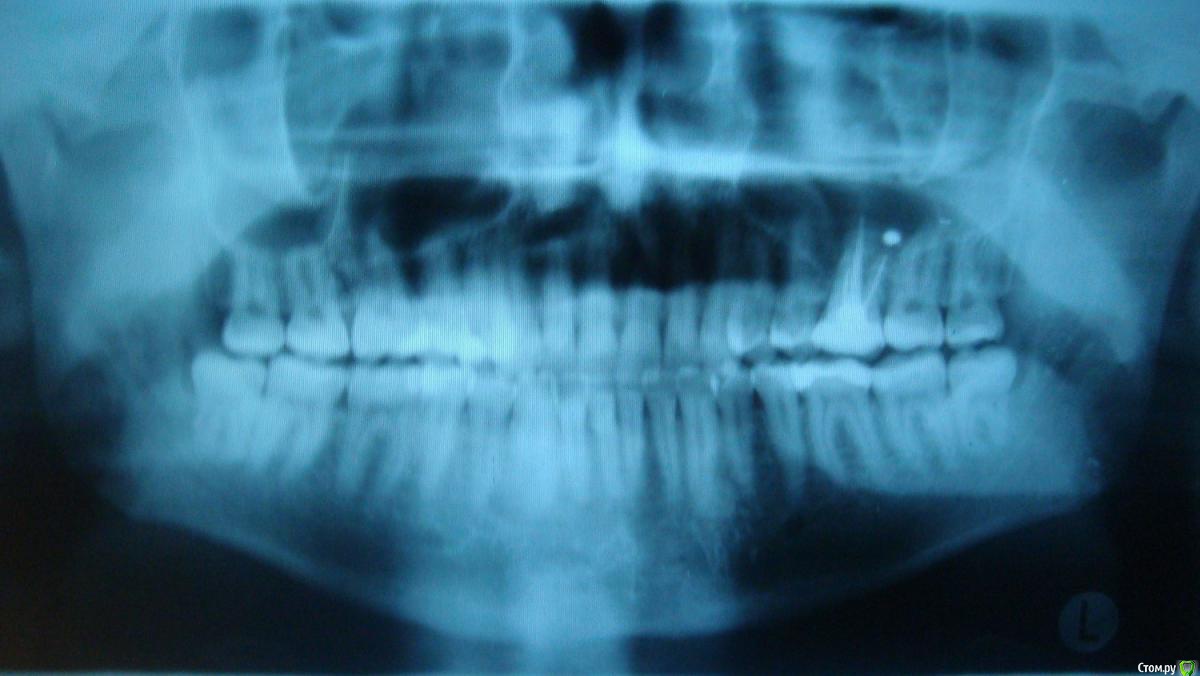

player543 Опубликовано 16 марта, 2015 Поделиться Опубликовано 16 марта, 2015 Здравствуйте.У меня иногда болит зуб при надавливании во время еды. Иногда несколько дней вообще не болит, в другой день при надавливании при каждом приеме пищи.Этот зуб был вылечен (пульпит) лет 7 назад, не помню делали ли рентген для проверки лечения.Эта нерегулярная боль при надавливании уже пару лет (и вроде бы не ухудшается). Помню что в течение года после лечения зуб болел при наклоне головы (но тоже не всегда). Прежде всего хочу разобраться в чем проблема зуба. Несколько стоматологов говорили что все из-за того, что пломбировочный материал попал в гайморову пазуху, предлагали идти к ЧЛХ и как-то там это "вычищать". Последний врач сказал что там канал до конца не заполнен и там живет инфекция. Почему-то сказал что нужно удалять зуб, а я не спросил почему.Ваше мнение в чем проблема зуба? И второе - как его лечить? Просто перелечивание каналов? Можно ли перелечить только 1 канал или только все сразу? Этот зуб был восстановлен более чем на 1/2 если это важно. Ссылка на комментарий

Гарриевич Опубликовано 16 марта, 2015 Поделиться Опубликовано 16 марта, 2015 Лечить можно двумя путями1- перелечивать все корневые каналы2- только каналы передне-щечного корня Ссылка на комментарий

red_butler Опубликовано 17 марта, 2015 Поделиться Опубликовано 17 марта, 2015 Для начала хорошо бы сделать Кт, и посмотреть верхнечелюстной синус. Далее повторное лечение с последующим протезированием. Точный объем лечения будет понятен в процессе.Показаний к удалению не увидел Ссылка на комментарий